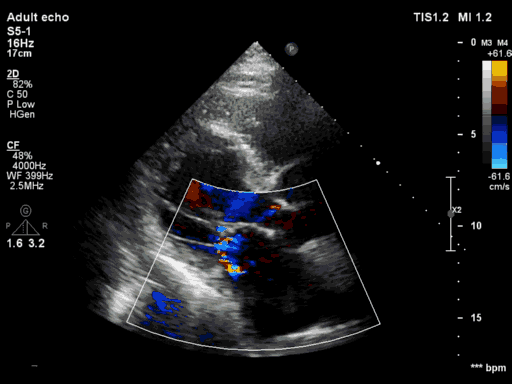

3月30日患者先在全麻下进行TEE(经食道超声心动图)再次评估瓣膜情况(视频4、视频5、视频6 ),确定为二尖瓣前组乳头肌断裂致二尖瓣前瓣脱垂并重度返流,其脱垂部位、瓣叶结构、瓣口面积等适合进行二尖瓣夹合术。术中IABP辅助,ECMO湿备,穿刺右侧股静脉,在TEE指导下顺利穿刺房间隔,随后送入二尖瓣夹合系统,在超声指导下于二尖瓣A2/P2区植入一枚Mitraclip XTR夹合器(视频7),术后TEE评估返流程度从5+降至1+(视频8 ),夹合结果满意,二尖瓣呈双孔启闭(视频9 ),术后二尖瓣平均跨瓣压差1mmHg(图1),收缩期肺静脉返流消失(图2 ),手术总耗时80min。香港亚洲医疗中心林逸贤教授通过视频连线进行手术全程技术支持。

图2